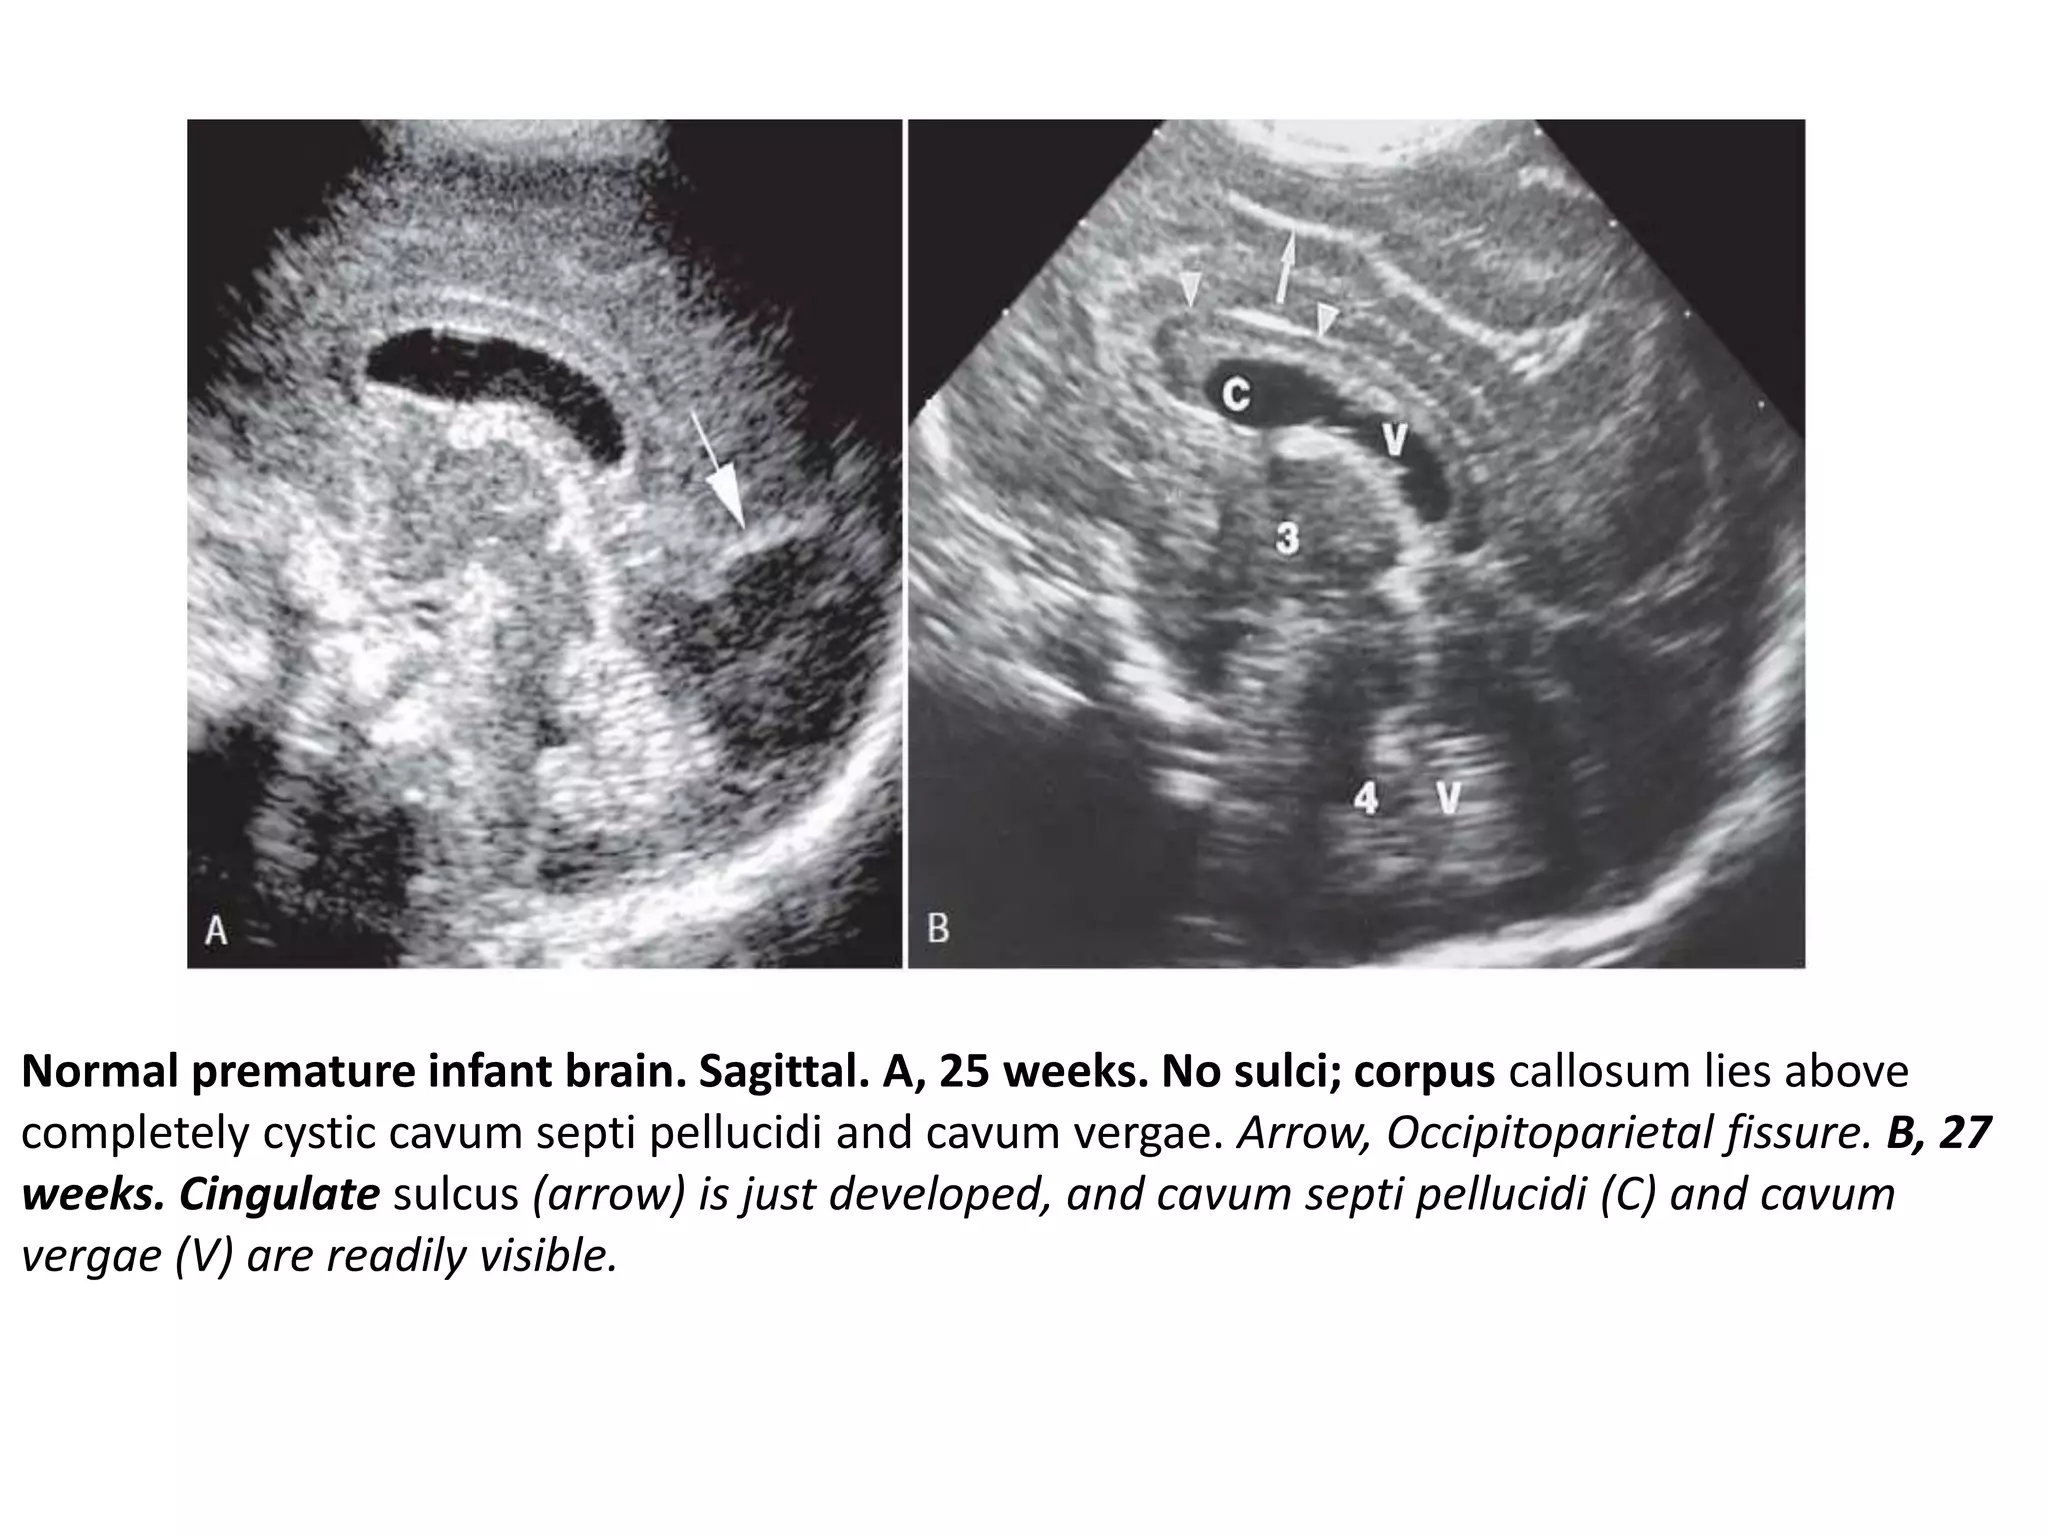

Normal premature infant brain. Sagittal. A, 25 weeks. No sulci; corpus callosum lies above

completely cystic cavum septi pellucidi and cavum vergae. Arrow, Occipitoparietal fissure. B, 27

weeks. Cingulate sulcus (arrow) is just developed, and cavum septi pellucidi (C) and cavum

vergae (V) are readily visible.

C, 30 weeks. Cingulate sulcus (short arrow) has a few branches. Long arrow, Cavum velum

interpositum.

Normal premature infantbrain. Sagittal. A, 25 weeks. No sulci; corpus callosum lies above completely cystic cavum septi pellucidi and cavum vergae. Arrow, Occipitoparietal fissure. B, 27 weeks. Cingulate sulcus (arrow) is just developed, and cavum septi pellucidi (C) and cavum vergae (V) are readily visible.

C, 30 weeks.Cingulate sulcus (short arrow) has a few branches. Long arrow, Cavum velum interpositum. •represents a potential space above the choroid in the roof of the third ventricle and below the columns of the fornices. •may appear as an anechoic, inverted, helmetlike space just inferior and posterior to the splenium in the pineal region Cavum velum interpositum